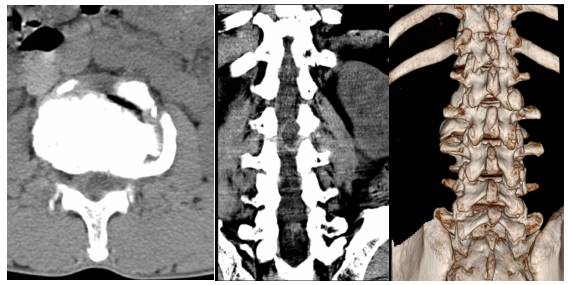

入院后查腰椎CT及腰椎增强MRI(图1)、(图2)。显示占位位于腰2椎体水平左侧腰1/2关节突内侧硬膜外,诊断首先考虑关节滑膜囊肿,囊性神经鞘瘤可能性较小。科室讨论,根据病灶位置及性质,拟行经皮脊柱内镜下探查,明确病灶性质,若术中探明属神经鞘瘤也可转显微开放手术。完善必要检查,与患者及家属沟通,知情同意后行脊柱内镜下经椎板间入路椎管探查+囊肿切除术。

图2. 腰椎CT平扫,腰2椎体水平椎管内占位,病灶病灶类圆形,边界清晰,位于椎管左侧膜外间隙,病灶平均密度约15-20Hu。囊壁菲薄均匀。

腰椎关节滑膜囊肿的诊断主要依靠CT和MRI[2]。腰椎X线片对腰椎关节滑膜囊肿的诊断价值有限,CT扫描可见关节突旁邻近黄韧带的硬膜外肿块,边缘密度略高,压迫硬膜囊和神经根,30%的囊肿边缘可见钙化,有的囊肿内可见低密度类气体空泡征。MRI对腰椎关节滑膜囊肿的诊断价值较高,能清晰显示囊肿的位置和大小,所有囊肿在MRI上均表现为边界清晰的硬膜外肿块,由于囊内容物的不同,在MRI上信号也呈多样性。囊壁结构在T1、T2加权像均为低信号,增强扫描可见非均质强化,它能很好的显示囊肿与腰椎关节的关系,确定硬膜外囊肿的来源及囊内容物的性质,占位位于硬膜外及椎孔未见明显扩大是其与腰椎囊性神经鞘瘤主要影像学鉴别要点。腰椎关节滑膜囊肿相关临床症状的轻重程度与囊肿大小、部位及邻近组织有关。小囊肿无明显症状,当囊肿逐渐增大突入椎管内压迫硬膜囊或神经根而引发类似腰椎间盘突出症和腰椎管狭窄症的顽固性腰痛、下肢放射痛和间歇性跛行,甚至马尾综合征。